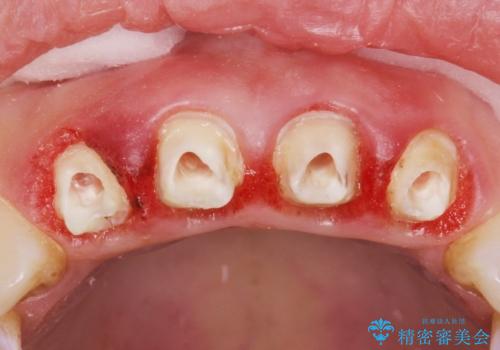

- 全顎的な重度歯周病の患者様です。

骨吸収の進行している右下臼歯部に、再生療法(骨を増やす手術))を行いました。

埋伏していた親知らず、保存不可能な右下の一番奥の歯(右下7)、状態の悪い犬歯(右下3)は抜歯しております。